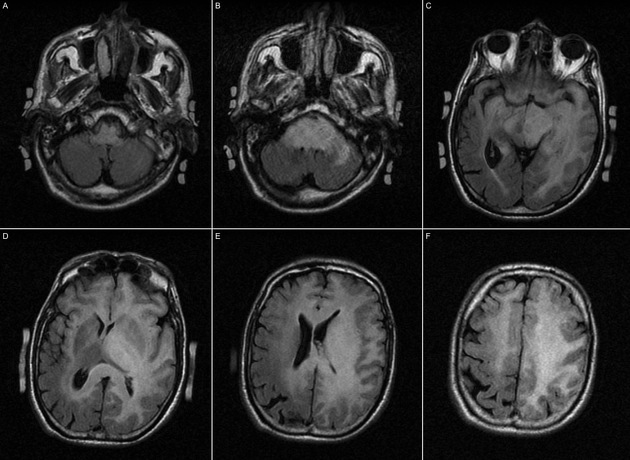

Imaging features of gliomatosis cerebri?

1. It an uncommon growth pattern of diffuse gliomas (infiltrating astrocytoma) that involves at least three lobes by definition, has frequent bilateral growth and may extend to infratentorial structures.

Patients present with headaches, seizures, focal neuro deficits.

1. CT: can be normal as lesions are often isodense to normal brain parenchyma. There is a relative lack of mass effect and distortion compared to the

extensiveness of involvement. There may be an ill-defined asymmetry or subtle hypoattenuation of the involved brain parenchyma.

2. MRI: Mass effect and enhancement are often minimal despite large portions of the brain being involved. There is a loss of grey-white matter differentiation and diffuse gyral thickening.

Diffuse T1 and T2 prolongation throughout both white and grey matter:

T1: iso to hypointense to grey matter 1

T2: hyperintense to grey matter 1

T1 C+ (Gd): typically no or minimal enhancement

DWI: usually no restriction